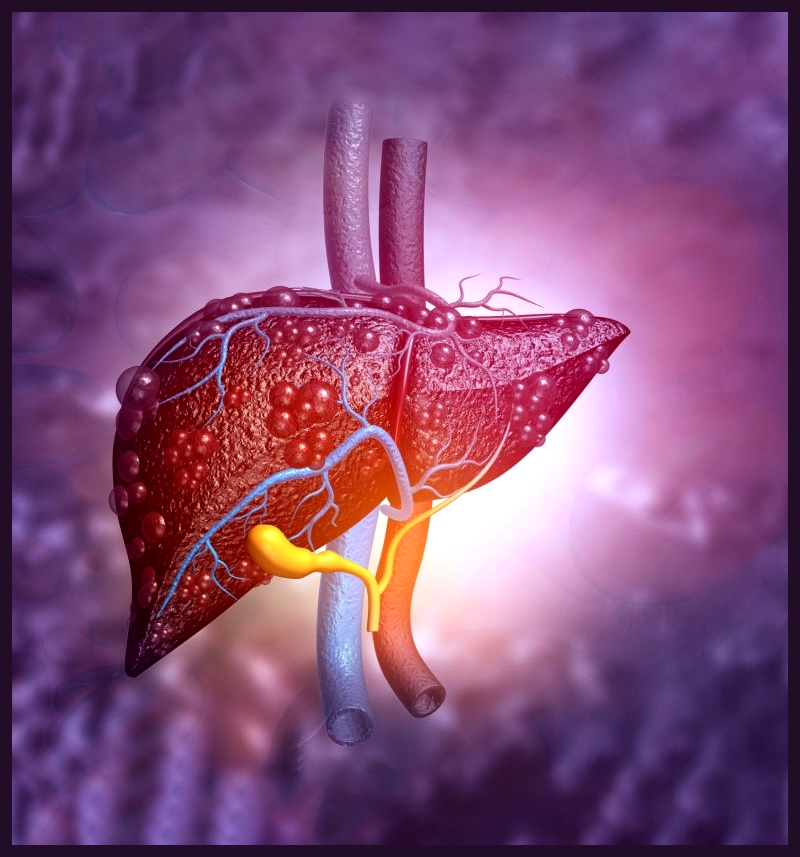

PBC a chronic disease characterized by progressive inflammation and destruction of small bile ducts within the liver. The bile ducts transport bile from the liver to the intestine for the absorption of fat and elimination of waste products.